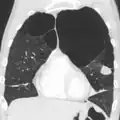

A chest X-ray is not useful to establish a diagnosis of COPD, but it is of use in either excluding other conditions or including comorbidities such as pulmonary fibrosis and bronchiectasis. Characteristic signs of COPD on X-ray include hyperinflation (shown by a flattened diaphragm and an increased retrosternal air space) and lung hyperlucency.[5] A saber-sheath trachea may also be shown that is indicative of COPD.[111]

Chest X-ray demonstrating severe COPD, displaying small heart size in comparison to the lungs